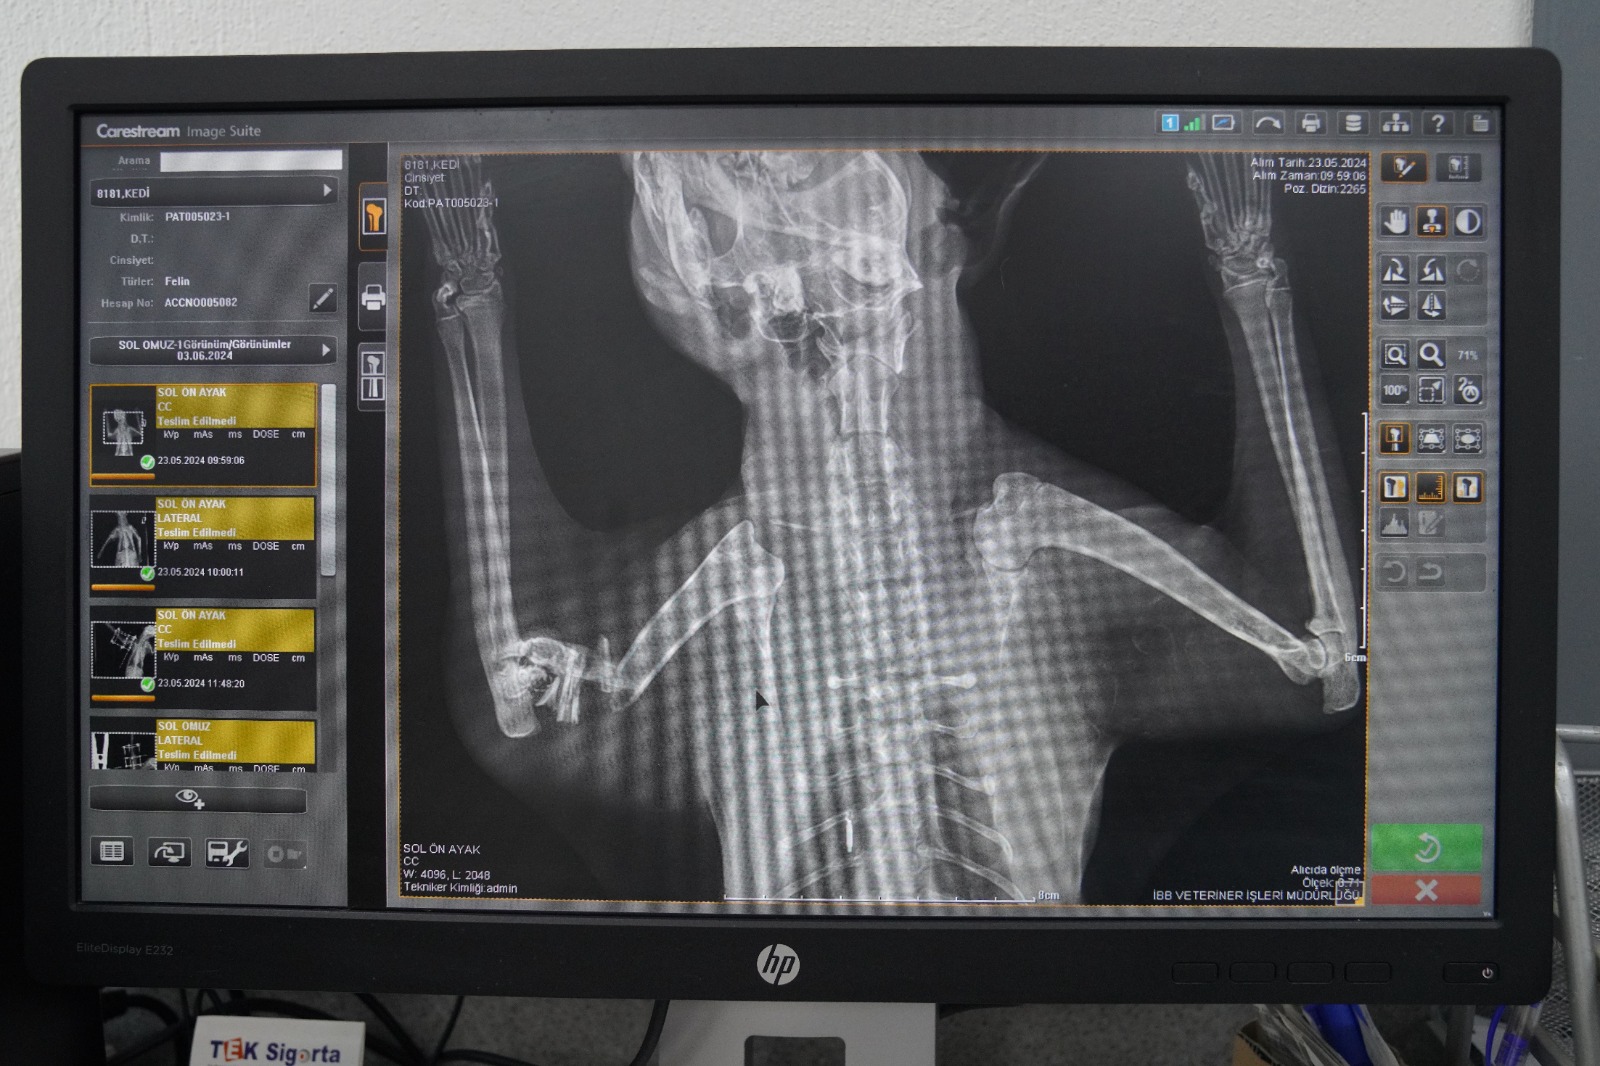

Ameliyat hakkında bilgi veren Veteriner Hekim Mehmet Uysal, ortopedi biriminde kedinin bacağının durumunu tespit ettiklerini belirterek, “Bacağının ciddi şekilde parçalandığını gördük. Burada sağlığına kavuşması için hemen gerekli cerrahi tedaviyi uyguladık. Bacağında parçalanan kemikleri özel bir aparatla sabitledik.

Güvenli bir yöntem olduğu için bunu tercih ettik. Kedimiz 25 gündür bu şekilde tedavi altında. Bir süre sonra bu taktığımız aparatın kırıklar üzerindeki etkisine bakacağız. Bacak iyileşmiş olursa çıkaracağız. Şu anda sağlığı ile alakalı bir problemi yok. Keyfi yerinde. Bacağını nasıl kullanacağını öğreniyor diyebilirim” diye konuştu.